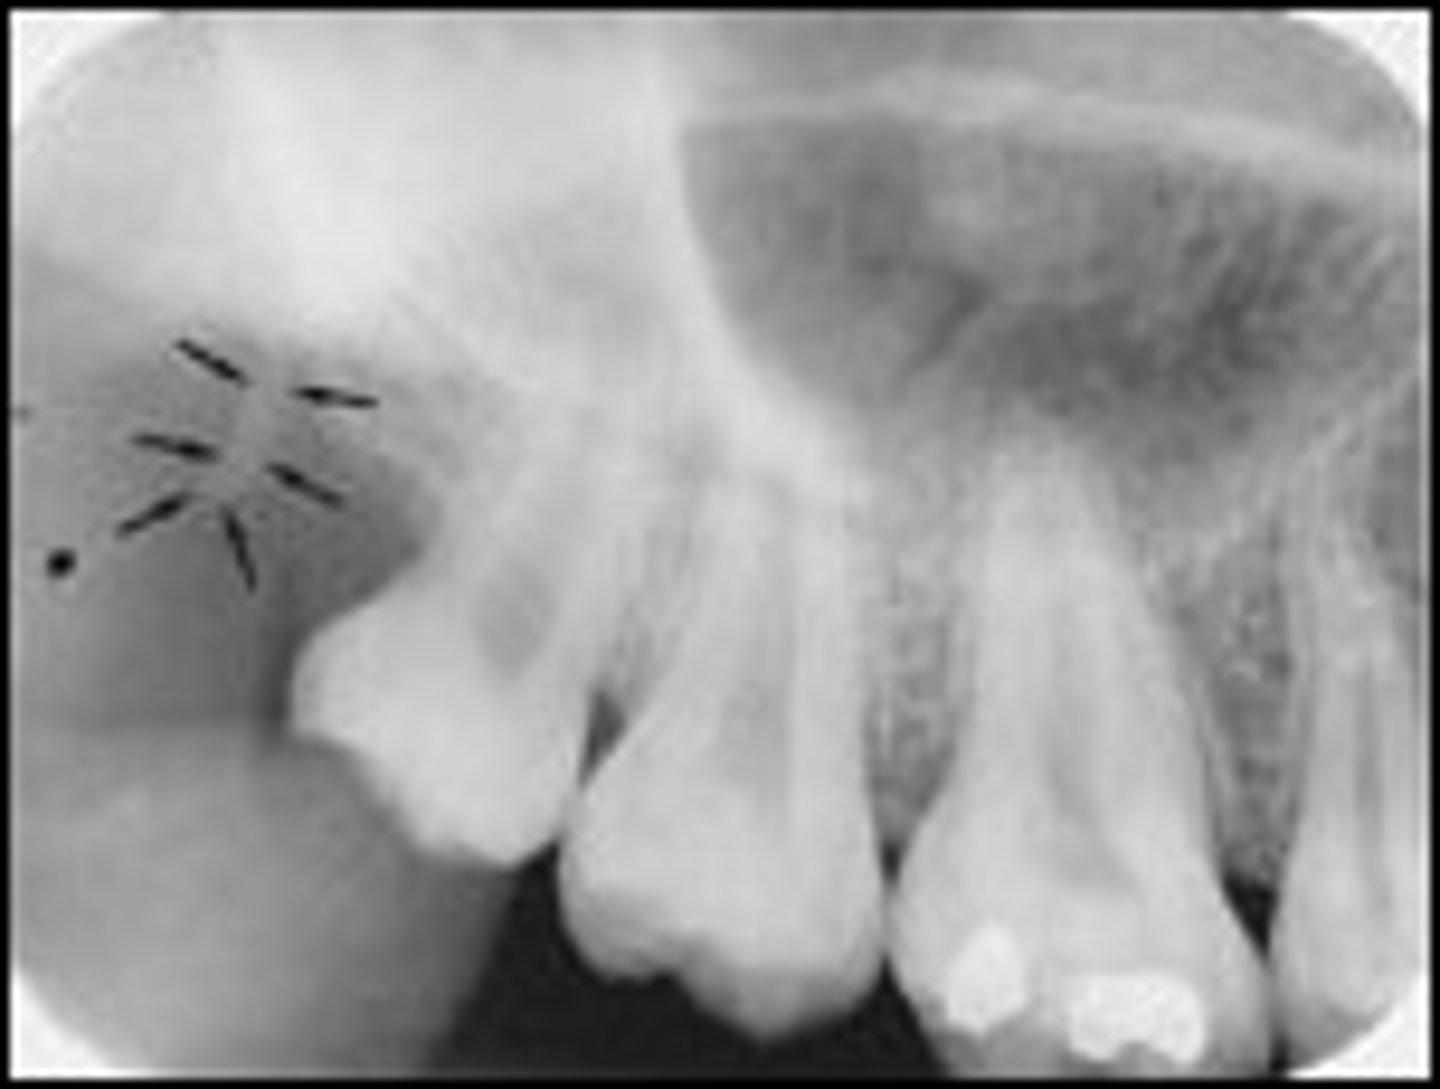

External oblique ridge

What is the radiopaque structure seen here?